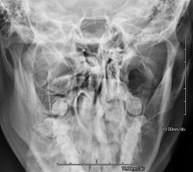

- RX Cráneo

Técnica mediante la cual, utilizando rayos X, se obtienen imágenes del cráneo para su estudio. Indicaciones: traumatismo, cierre precoz de suturas craneales. - RX Senos Paranasales

Técnica mediante la cual, utilizando rayos X, se obtienen imágenes de los senos paranasales para su estudio. Indicaciones: dificultad respiratoria nasal, tos crónica, cefalea, mucosidad. - RX ATM (Articulación Temporo-Mandibular)

Técnica mediante la cual, utilizando rayos X, se obtienen imágenes de las órbitas para su estudio. Indicaciones: cuerpo extraño ocular, traumatismo, infecciones. - RX Mandibular

Técnica mediante la cual, utilizando rayos X, se obtienen imágenes de la mandíbula para su estudio. Indicaciones: traumatismo, anomalías congénitas. - RX Laringe